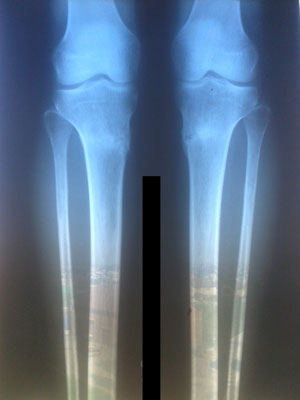

Рентген контроль в 1,5 месяца с момента снятия аппаратов.

Всё в норме! Разрешено все нагрузки без ограничения, каблуки любых размеров! Фото на каблуках за Вами!